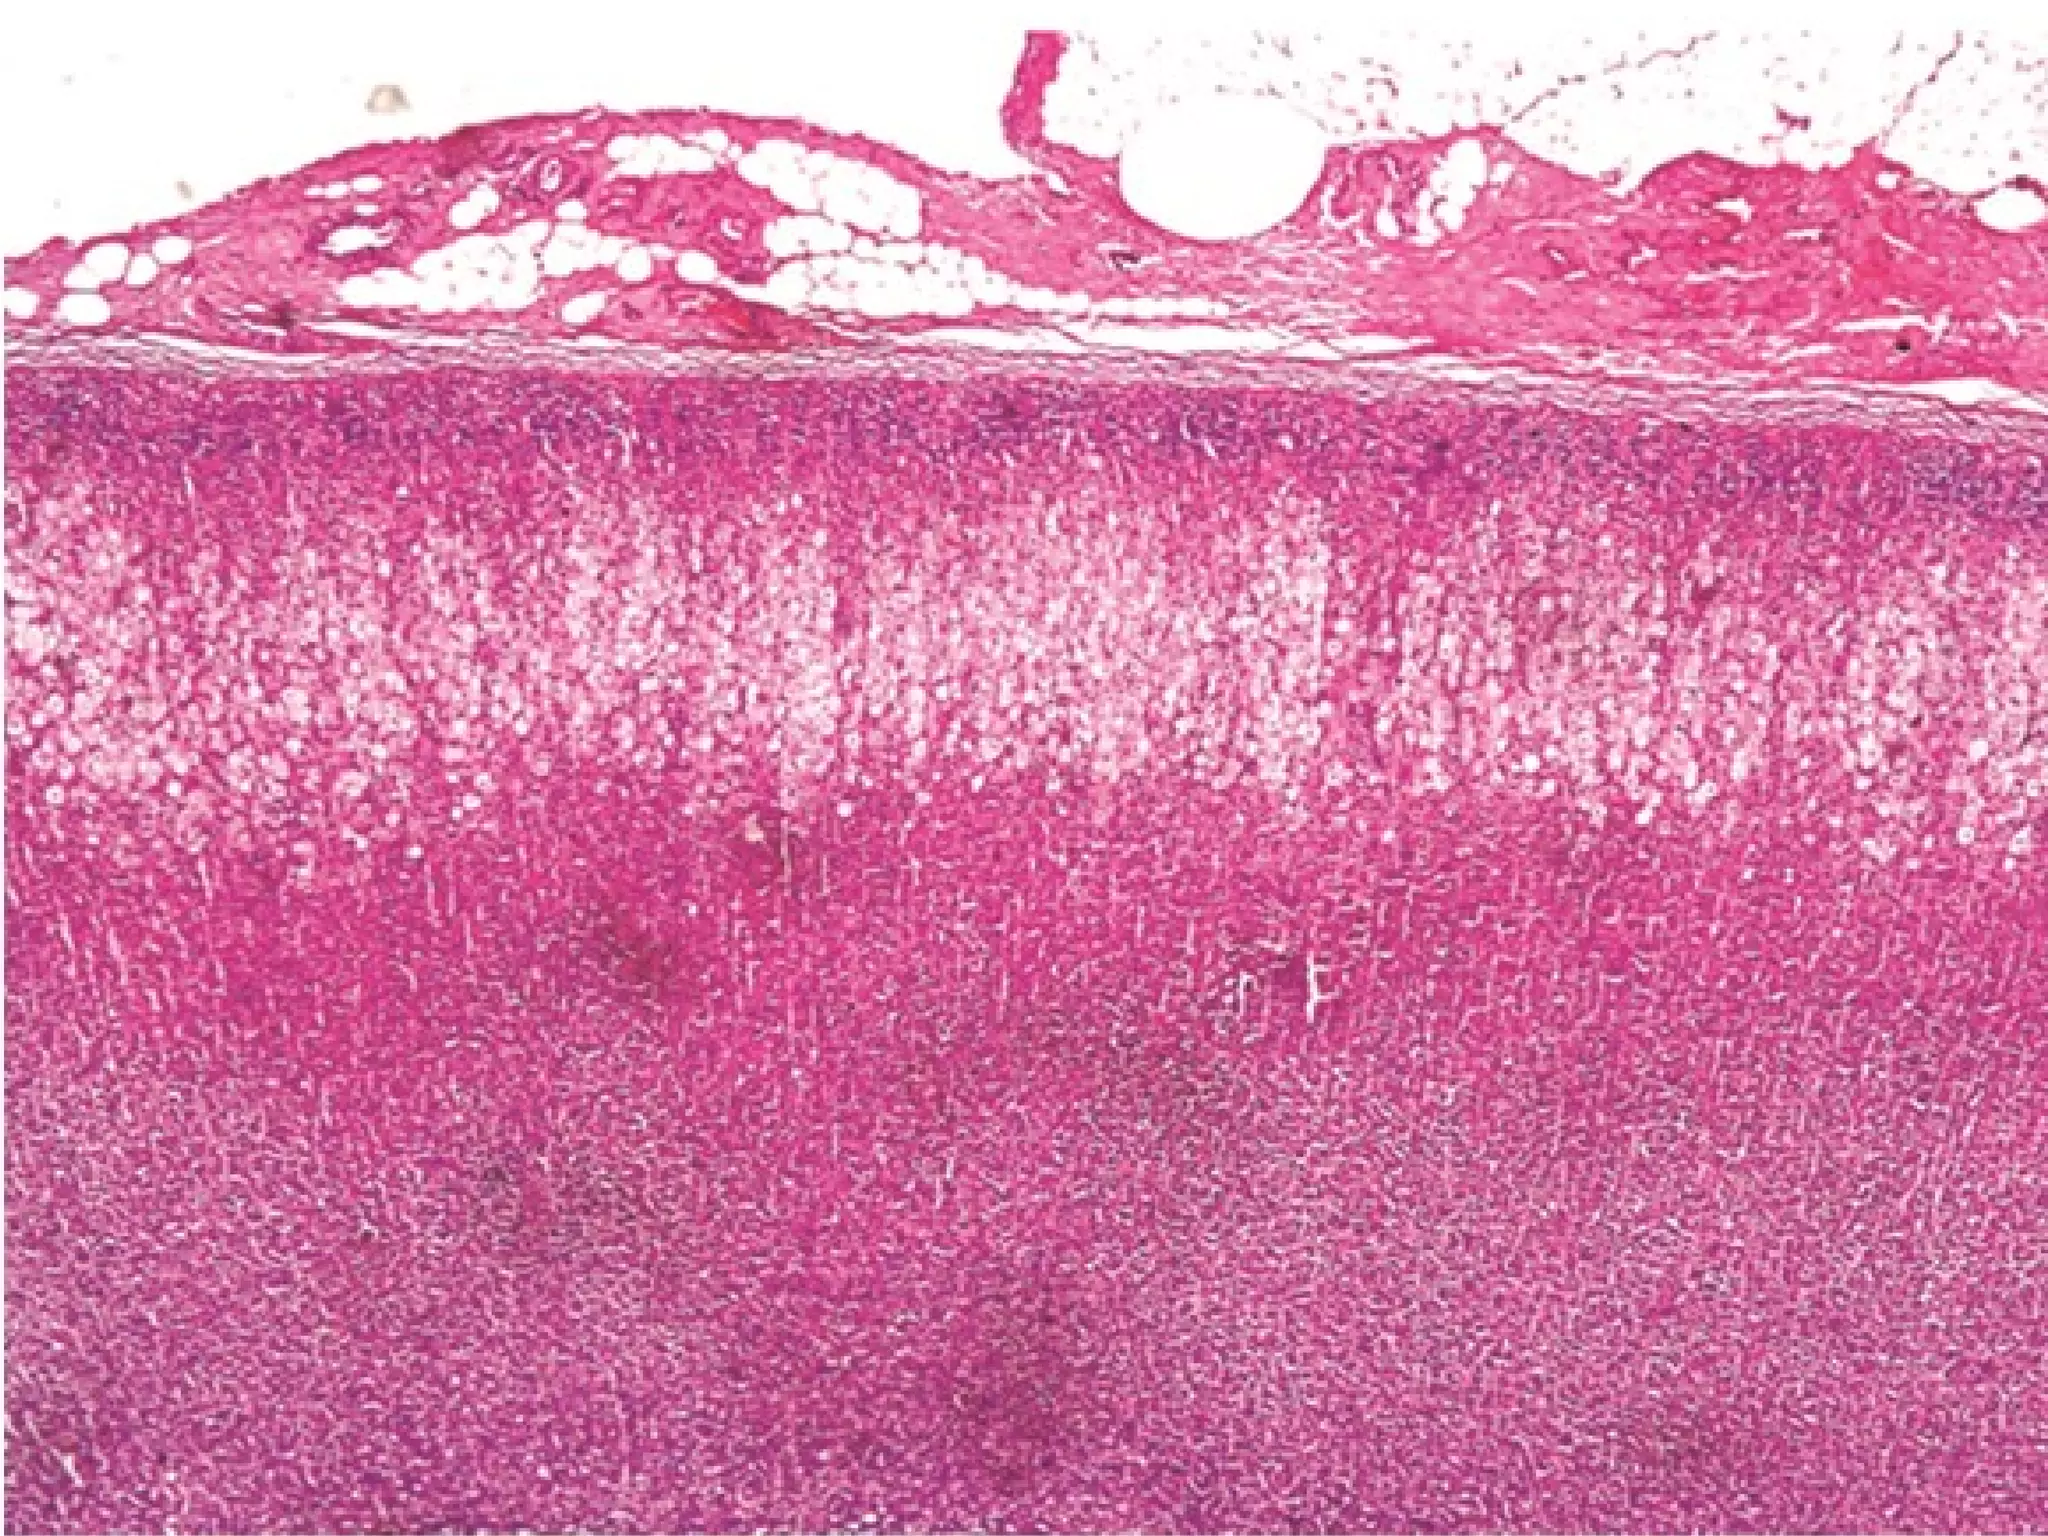

This document outlines several human body systems including the vascular, lymphatic, respiratory, digestive, and endocrine systems. It describes the trachea and lungs in the respiratory system, the oral cavity and digestive glands in the digestive system, and mentions the parotid, pancreas, and classic hepatic lobule in relation to the digestive system and endocrine glands.